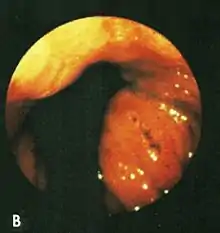

Cameron lesions. A long linear erosion and smaller non-linear erosions on the crests of inflamed gastric folds at the level of the diaphragm.

Based on their surgical observations, Windsor and Collis in 1967[4] proposed that blood loss was due to local trauma to the stomach where it rides to and fro in the hiatus on respiration. Boutelier et al.[8] noted on gastroscopy ulcers and erosions at the level of the neck of the hernia in individuals with acute and chronic bleeding, but no detailed description was given. Cameron and Higgins in 1986[1] described linear gastric erosions, later called "Cameron lesions", in people with x-rays showing one-third or more of the stomach above the diaphragm.[9][10][11][12][13][14][15] (figure 1). Over 6 years, Cameron and Higgins studied 109 persons with large hiatal hernias, 55 with anemia and 54 without anemia, at esophagogastroduodenoscopy. Cameron lesions, often multiple, were found at or near the level where the herniated stomach was constricted by the diaphragm. The lesions were typically white, superficial, linear, and oriented along the crests of inflamed appearing mucosal folds (figure 2). Small amounts of blood were often seen on the lesions (Fig 3). Mucosal folds at the diaphragm level were often seen rubbing against each other on respiration (Fig 4). It was proposed that the lesions were caused by mechanical trauma at the level of constriction by the diaphragm [1] Cameron lesions were found in 42% of persons with anemia compared to 24% in those without anemia, a statistically significant difference, p<0.05. Spots of fresh or clotted blood were seen on the lesions in 25% of persons with anemia compared to 7% without anemia, also a significant difference, p<0.05. In the 109 persons in this study, 15 had reflux esophagitis, 11 had peptic ulcers, and 7 had Barrett's esophagus, but none of these findings correlated with anemia. Thus, in people with large hernias, Cameron lesions with evidence of slow bleeding were associated with iron deficiency anemia.